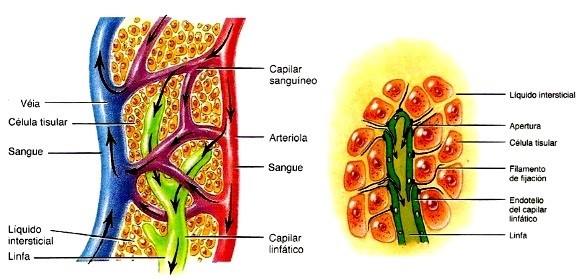

O Sistema Linfático de modo estrutural, assemelha-se ao sistema cardiovascular, uma vez que o mesmo possui vasos que são responsáveis por atuar na remoção de fluidos que se encontram em excesso nos tecidos, bem como absorver ácidos graxos e garantir o transporte para o sistema circulatório (5).

Como dito outrora, e de importante fixação, apesar de trabalhar de forma consonante ao sistema cardiovascular, a função primordial do sistema linfático é a remoção de líquidos dos espaços intersticiais, sua reciclagem através da retirada de proteínas e ácidos graxos e sua devolução a corrente sanguínea.

Tais líquidos, uma vez dentro dos capilares linfáticos são chamados de Linfa, que é um líquido viscoso e transparente com composição semelhante à do plasma sanguíneo, mas com uma baixa concentração de proteínas.

Nele, ainda há uma grande concentração de leucócitos, em sua maioria linfócitos, já que o próprio Sistema Linfático participa diretamente na resposta imunológica do organismo (6).

À Esquerda: Interação do Sistema Linfático com o Sistema Cardiovascular, bem como à direita: Estrutura do Sistema Linfático e Espaço Intersticial.